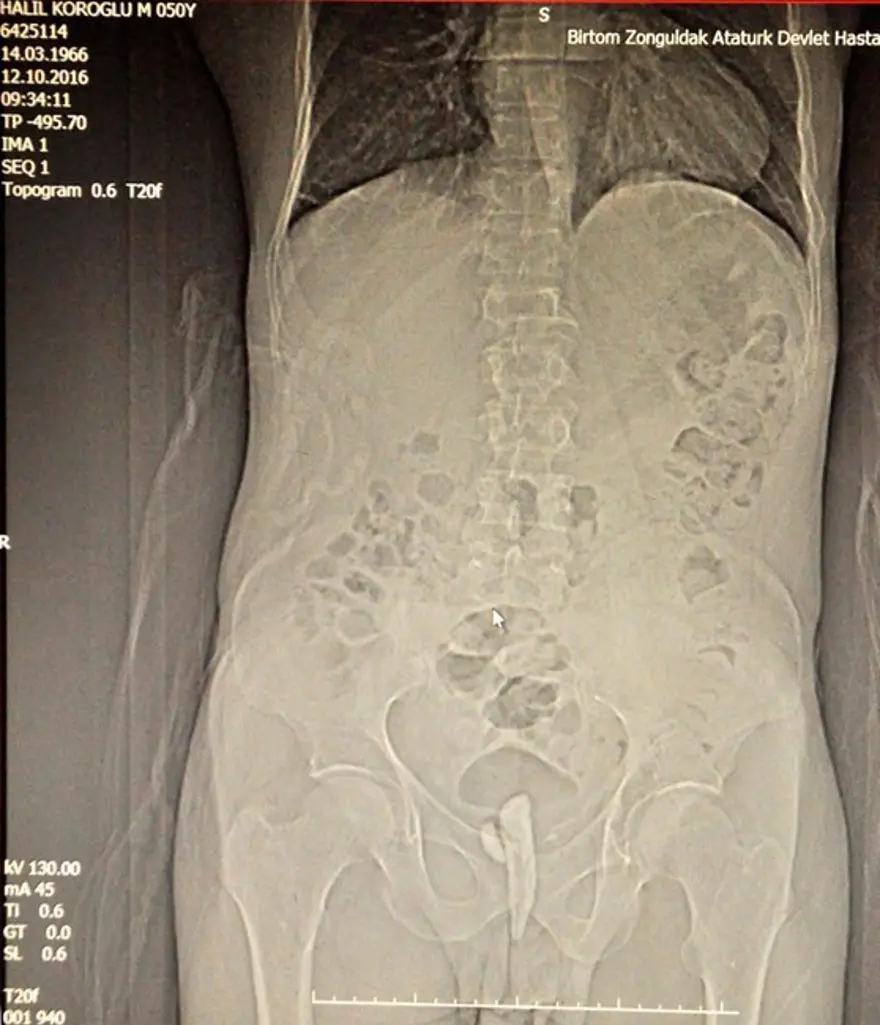

Zonguldak'ta bir boru fabrikasında işçi olan 50 yaşındaki Halil Köroğlu, yüksek ateş ve idrar yapma zorluğu şikayetiyle geçen 13 Ekim'de Zonguldak Atatürk Devlet Hastanesi'ne gitti.

Üroloji Doktoru Metin Kılıç'ın yaptığı kontrolde, Köroğlu'nun idrar kanalı ve kesesinde bir cisim saptandı. 20 Ekim'de hastanede yaklaşık 2 saat süren operasyonla idrar kanalından keseye doğru uzanan 8 santim uzunluğundaki parça alındı. Çıkarılan cismin odun parçası olduğu ve etrafının taşlandığı belirlendi.